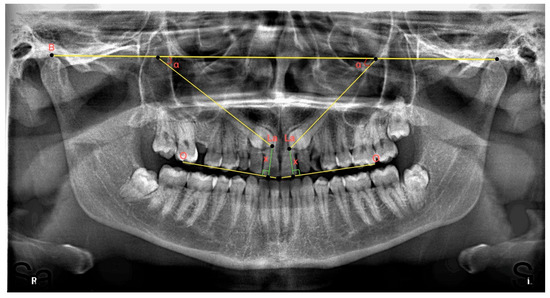

In determining the mesiodistal angular positions of impacted maxillary canines, the bicondylar plane drawn from the uppermost and anterior points of the right and left condyles was created as a fixed reference [22]. The medial angle between this reference line and the long axis of the canine was measured and recorded (see Figure 2).

A panoramic radiograph showing the angle between the right and left impacted maxillary canines and the bicondylar plane, separately. B: Bicondylar plane, the junction of the uppermost and anterior points of the condyles; La: line passing through the long axis of the canines; O: occlusal plane; x: perpendicular distance of the cusp apex of the canine from the occlusal plane; and α: medial angle between the long axis of the canine and the bicondylar plane.

On panoramic radiographs, the distance of the impacted maxillary canines to the occlusal plane was recorded by measuring the distance of the vertical line descending from the canine cusp apex to the occlusal plane [23] drawn between the maxillary central incisor and the mesial tubercle of the maxillary permanent first molar (see Figure 2).